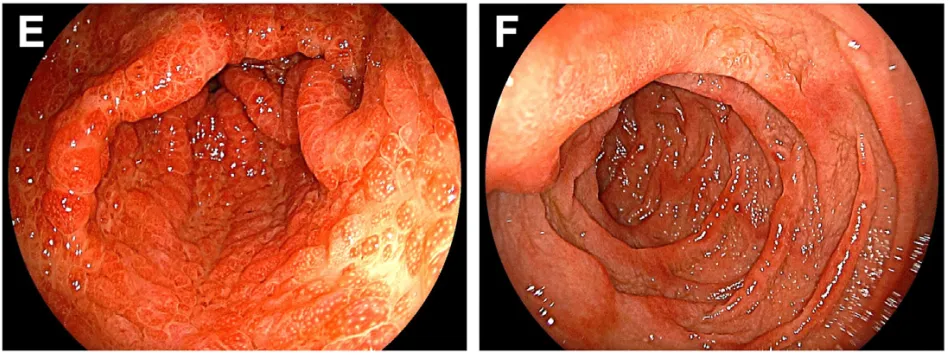

食管胃十二指肠镜检查见胃窦部多发小型红色半球状息肉(图E),十二指肠黏膜